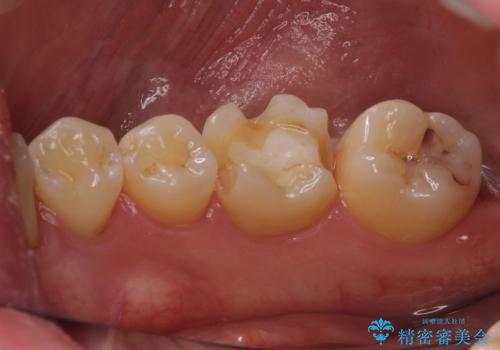

古い材料も虫歯もすべて除去して、根本からやりかえました。

咬む力が強いため、このままでは何度もセラミックとご自身の歯を割る可能性就寝時マウスピースの使用をご提案しました。患者様には、大変満足して頂きました。